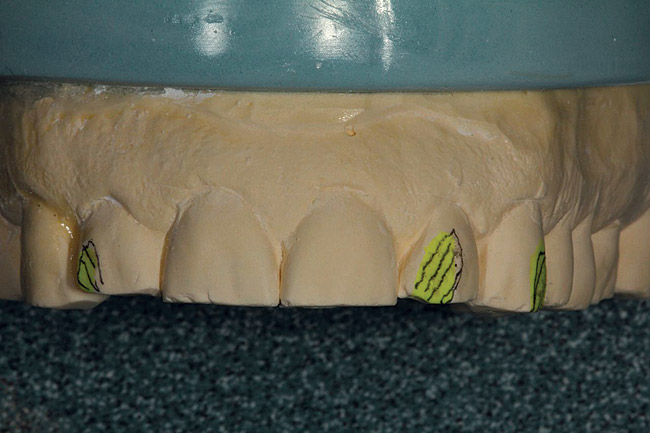

Figure 10  A green plastic reduction stent was vacuum-formed over the preoperative upper model.

Figure 10

Figure 11  The reduction guide was created.

Figure 11